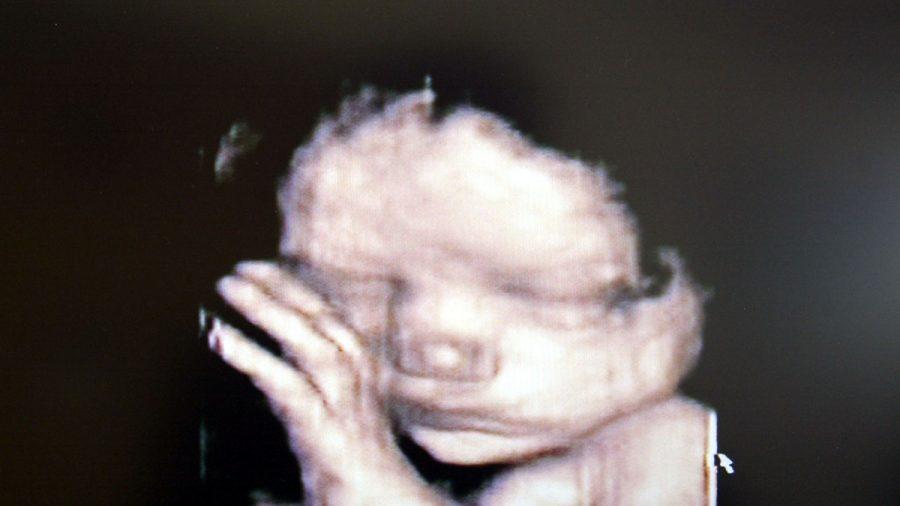

A federal judge said in a Jan. 22 ruling that the “heartbeat” abortion law, which would have banned nearly all abortions after babies in the womb had a detectable heartbeat, was unconstitutional.